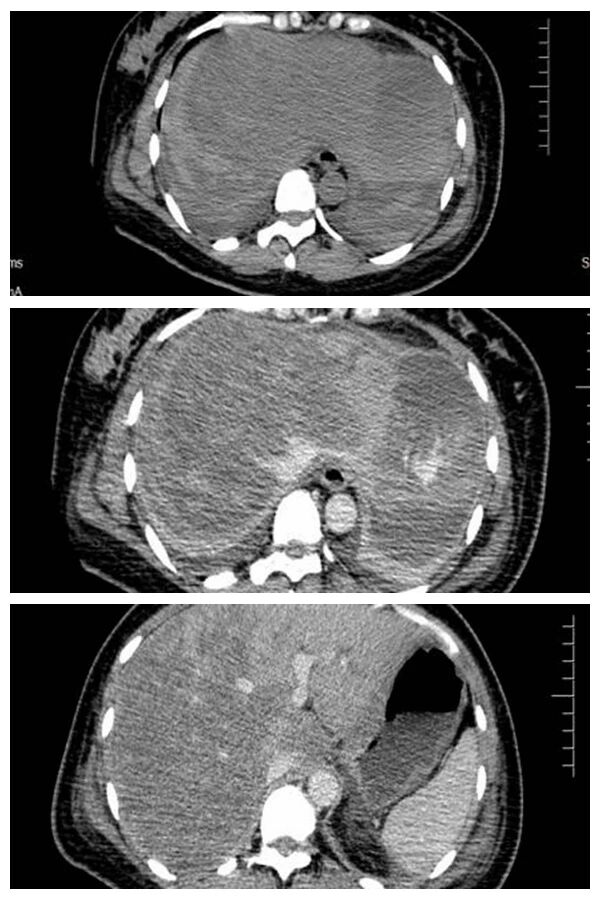

盡管輸注了近 1 萬毫升血液(相當(dāng)于全身血液置換 2 次),但血紅蛋白仍持續(xù)下降,腹腔積液從淡黃色變?yōu)檠?。多學(xué)科團(tuán)隊(duì)(MDT)會(huì)診后,為患者插管上呼吸機(jī),增強(qiáng) CT 檢查,最終確診:肝臟自發(fā)性破裂出血,腹腔盆腔積血;介入科團(tuán)隊(duì)緊急行血管造影,排除子宮、腸道等部位出血,將治療焦點(diǎn)鎖定肝臟。凌晨 3 點(diǎn),肝膽外科團(tuán)隊(duì)開展急診剖腹探查術(shù),發(fā)現(xiàn)肝臟表面兩處 12cm、15cm 巨大裂口。專家們運(yùn)用電凝、縫扎、填壓等技術(shù),歷經(jīng) 2 小時(shí)成功止血。